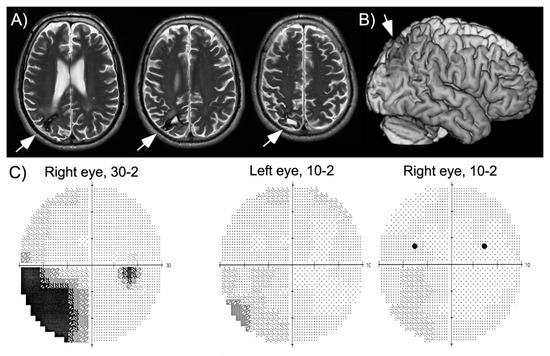

HG is a 60-year-old, well-educated man who suffered a right parietal hemorrhage four years before this study. He had a first neurological and neuropsychological examination within a week after his stroke, which showed partial sensory loss of the left arm, left inferior quadrantanopia, moderate spatial neglect and visual-constructive deficits. While hospitalized, the patient had a series of partial epileptic seizures whose focus was localized to the right parietal lobe. He quickly recovered arm sensation and part of his deficits of spatial cognition, though he was unable to take up driving and work due to persistent fatigue. At the time of this study his neuropsychological assessment revealed a slight, but significant bias on line bisection, visual-constructive deficits as well as increased reaction times to stimuli shown in his left visual hemifield and in visual search (Table 1), consistent with his report of slight spatial neglect in activities of daily living (e.g., orienting in new environments, bumping occasionally into people on his left, searching for his keys). A magnetic resonance imaging (MRI) scan performed two years after his hemorrhage showed local damage in the superior part of the posterior parietal cortex and underlying white matter (Figure 1). The patient was seen three years following his hemorrhage for a routine examination. At this time, he still had partial left inferior quadrantanopia, though the central ~10° of vision were preserved (Figure 1). He had been without seizures for more than two years, but continued to receive anticonvulsant medication (carbamazepine).

Figure 1.

Magnetic resonance imaging (MRI) scan and visual field plot of the patient. (A) Axial slices at three different levels of the parietal lobe (images shown according to radiological convention, left is on the right). (B) Three-dimensional reconstruction of the patient’s brain, showing the small lesion in the superior parietal cortex. (C) Visual field plots (Humphrey Perimeter; 30-2 plot: sensitivity tested up to 30 degrees into the left and right hemifield; 10-2 plots: sensitivity tested for the central 10 degrees; inter-stimulus distance was always two degrees). Testing of the sensitivity up to 30 degrees in the periphery shows incomplete left lower quadrantanopia. More detailed testing of the central 10 degrees shows intact central visual fields. The two black dots indicate positions where targets were presented.

The main finding of experiment 1 is that, for stimuli shown in his intact right hemifield, HG reported seeing a second stimulus in his left hemifield. This observation was true whether targets were presented in the upper or the lower quadrants (Figure 2). The patient never reported a left stimulus in target absent conditions, indicating that his illusory perception crucially depended on the presence of a target in the right hemifield. Further, although he appeared to have intact visual sensitivity at positions in the upper and lower left quadrant where targets were presented (as shown in his visual field plots, Figure 1), his performance for stimuli in the left inferior quadrant was lower than in the superior quadrant. This is contrary to many cases of palinopsia and polyopsia, who report illusory stimuli within visual scotomas. Another difference is the lack of persistence of the illusory image: while palinopsias and polyopsias typically appear and persist (often for seconds or even minutes) after disappearance of the stimulus that triggers illusory perception, here the illusory phenomenon was short-lasting, simultaneous with the right-sided target and more frequent at very short presentations. All these observations suggest a different underlying mechanism. One possibility is that HG used a conscious strategy, and that he inferred the presence of a left stimulus whenever his perception of the right stimulus was weak (in particular when stimuli were presented at 35 ms). This explanation becomes plausible if we assume that the patient is less confident about his sensations of stimuli shown in the left hemifield when stimuli are shown close to threshold. In the next experiment, we examined whether HG’s illusory perception was modulated by his focus of attention.